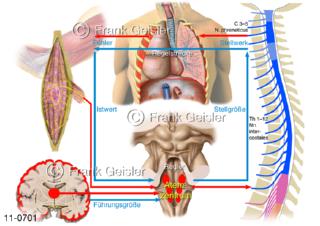

11-0701 Physiologie Atmung, Regelkreis physikalische Regulation Atemregulation